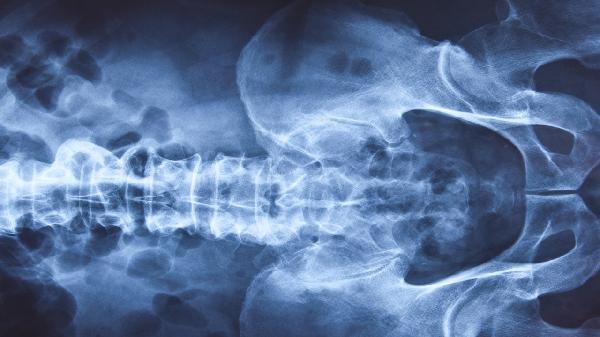

三维皮肤CT检查的准确度通常较高,能够清晰显示皮肤各层结构,对多种皮肤疾病的诊断具有重要参考价值。三维皮肤CT主要用于辅助诊断白癜风、银屑病、皮肤肿瘤等疾病,其成像原理是通过光学共聚焦技术实现皮肤断层扫描,可观察到传统病理切片难以捕捉的动态信息。

三维皮肤CT的优势在于无创性和实时性,检查过程中无须切割皮肤组织,避免了活检带来的创伤和感染风险。设备通过高分辨率成像可识别表皮层厚度变化、黑色素分布异常、真皮浅层炎症浸润等微观改变,对早期皮肤肿瘤的鉴别诊断尤为敏感。检查结果通常与组织病理学结果一致性较好,尤其在白癜风活动期判断、银屑病疗效评估中具有独特价值。多数情况下,医生会根据三维皮肤CT提供的细胞形态学特征结合临床表现进行综合判断。

三维皮肤CT的准确性可能受操作者经验、设备参数设置、皮肤部位等因素影响。特殊部位如眼睑、耳廓等曲面区域可能因探头贴合度不足导致图像质量下降。色素沉着严重的皮肤可能干扰光学信号接收,某些深层皮肤病变超出检测深度范围时需结合其他检查。对于直径过小的早期皮损或非典型病例,仍需通过皮肤活检进行最终确诊。